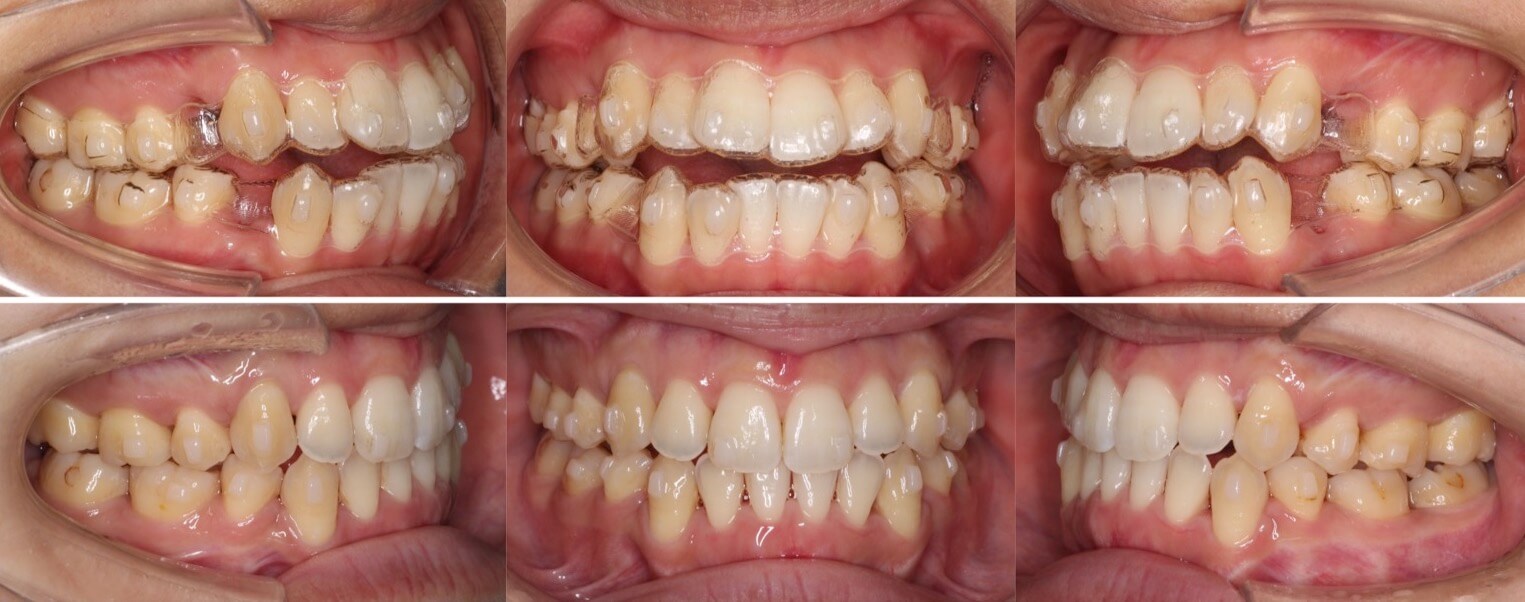

「男性は顔が引き締まる」

高校生男性・唇側矯正装置・下あご後退型

当初は、抜歯矯正治療にするかしないかで、治療方針に迷ったケースですが、最終的には患者さんの希望に沿って抜歯矯正治療にしました。歯の動きがゆっくりであったため、治療期間が3年を超えてしまいました。

<症例概要> 難易度:★★★★☆

主訴:口元の突出・前歯のガタツキ

年齢・性別:高校生男性

住まい:千葉県八千代市市

症状:下顎後退・叢生

治療方針:抜歯空隙の閉鎖(最大固定)

治療装置:唇側矯正装置

固定:歯科矯正用アンカースクリュー(頬側x2)

抜歯:上下第一小臼歯(計4本)

治療期間:3年4か月

リテーナー:上下プレートタイプ+フィックスタイプ

治療費用:968,000(税込)

代表的副作用:痛み・治療後の後戻り・歯根吸収・歯髄壊死・歯肉退縮